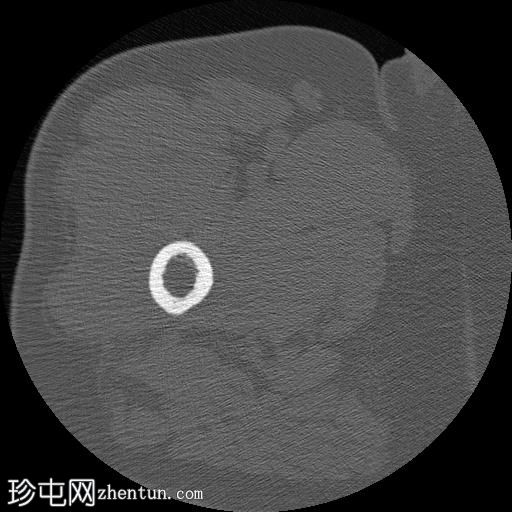

3.jpg

轴位

平扫

右股骨近端干骺端,股骨大转子下方可见一边界清晰的溶骨性病变。

未见皮质破坏及骨膜反应。